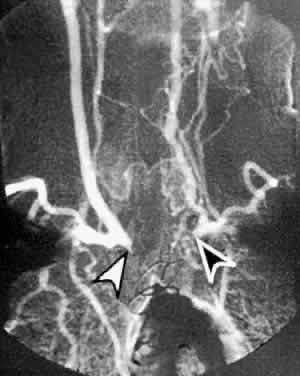

Ophthalmic symptoms, due to ocular hypoperfusion from occlusion of the carotid artery, are seen in 15% of cases.59 These ophthalmic changes may be identical to those of ocular ischemic syndrome caused by carotid atherosclerotic disease (see Figs. 5 and 6).60,61 Arteriography of the aortic arch region, showing smooth-walled areas of stenosis and dilation, is usually necessary to confirm the diagnosis (Fig. 11). Collateral circulation, due to the chronicity of the stenosis, is usually prominent.

Fig. 11. Digital subtraction thoracic angiogram of the aortic arch and its major branches in the same patient with Takayasu's arteritis as shown in Figures 5 and 6. The right common carotid artery shows nearly complete occlusion (white arrowhead). The left common carotid artery shows complete occlusion with extensive collateral flow (black arrowhead). (Courtesy Travis A. Meredith, MD, St. Louis MO)